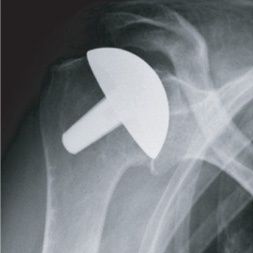

Schaftverankerte Prothese – Stielprothese: Die klassische Form der Schulterendoprothese. Ist der Oberarmkopf zu stark zerstört, erfolgt die Verankerung der Prothese mit Hilfe eines Stiels im Oberarmschaft. Verwendet werden zementierte oder zementfreie Implantate, je nach Knochenbeschaffenheit. Verschiede Stecksysteme erlauben das Aufsetzen unterschiedlicher Köpfe auf diesen Schaft, so dass eine anatomische Wiederherstellung des Gelenks erfolgt. Ggf. kann auch hier die Gelenkpfanne (Glenoid) mitersetzt werden.

Inverse Schulterprothesen: Besteht neben der Gelenkzerstörung eine starke Schädigung der Rotatorenmanschette, muss die fehlende Muskelfunktion durch eine besondere Konstruktion der Prothese ersetzt werden. Das Gelenk wird umgedreht. Die Kugel sitzt nun auf der ehemaligen Gelenkpfanne und der Oberarmkopf wird durch eine künstliche Pfanne ersetzt. Dadurch werden die Hebelarme an der Schulter so verändert, dass allein der Schulterkappenmuskel (Deltamuskel) eine gute Beweglichkeit der Schulter erzielen kann. Schwer geschädigte Schultergelenke können mit diesen Prothesensystemen sehr gut versorgt werden.